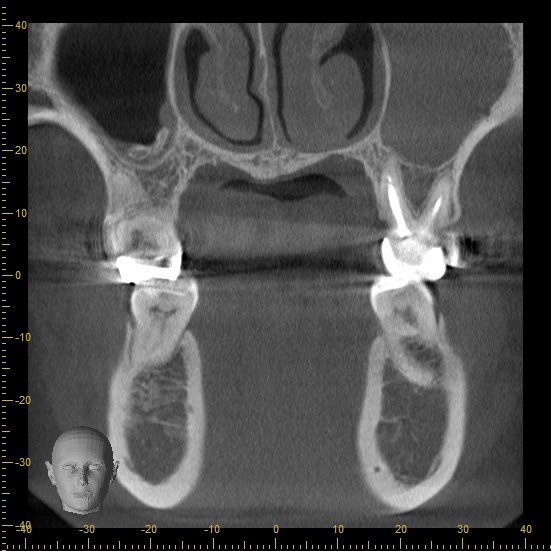

歯周病に罹患されている患者さんです。

当院に受診された際の最初のレントゲン写真です。

矢印で指している部分の骨が溶けてしまっています。

ここが歯周病が進行している部分です。

ということで、歯ぐきの中の歯石を取った後はどうなったのか。

治療の前後を見てみましょう。

治療前

治療後

いかがでしょうか。

レントゲンで見ると、歯周病により一度溶けてしまった骨がまた少しずつ回復しているのがわかります。